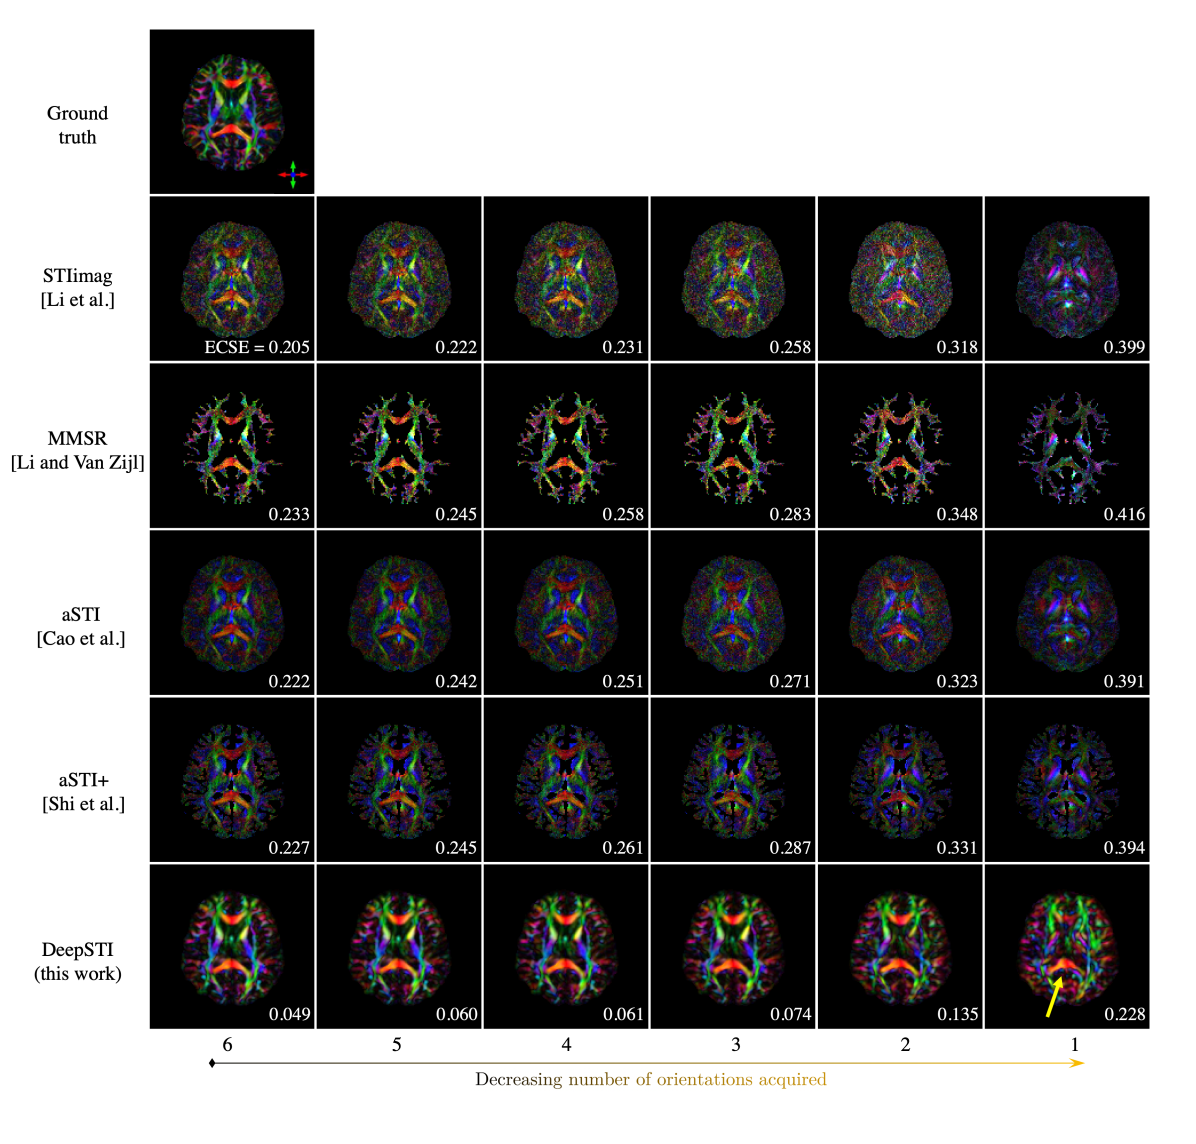

Refer to caption

Figure 2: Magnetic susceptibility anisotropy (MSA) weighted PEV maps estimated from measurements at decreasing number of head orientations simulated from a brain phantom with 1.5 mm resolution. On the lower-right corner of each image shows the eigenvector cosine similarity error (ECSE) of estimated PEV as defined in Section 3.5.

Figure 2 presents the estimated principal eigenvector (PEV) maps obtained from different numbers of head orientations (from 6 to 1) using simulated measurements of a brain phantom with 1.5 mm isotropic resolution. All STI PEV maps are weighted by the magnetic susceptibility anisotropy (MSA) estimated by each respective method. Note that while the visual results are affected by both MSA and PEV estimation, the ECSE metric reflects only PEV estimation accuracy. A significant improvement can be observed in the results yielded by DeepSTI. Compared to the existing methods, more accurate PEV estimation is achieved by DeepSTI across all numbers of head orientations. Even when the number of orientations decreases from 6 to 2, DeepSTI continues to produce highly accurate results (as measured by ECSE) that match well with the ground-truth, while the estimations from other methods deteriorate drastically. In the extreme case of reconstruction from only one head orientation, DeepSTI can still recover some structures visible in the ground-truth PEV map, notably in the corpus callosum splenium (indicated by yellow arrow), while the other methods fail to produce any useful reconstructions. These results demonstrate the potential of accurate fiber direction mapping using STI when sampling a much smaller number of head orientations than previously reported.